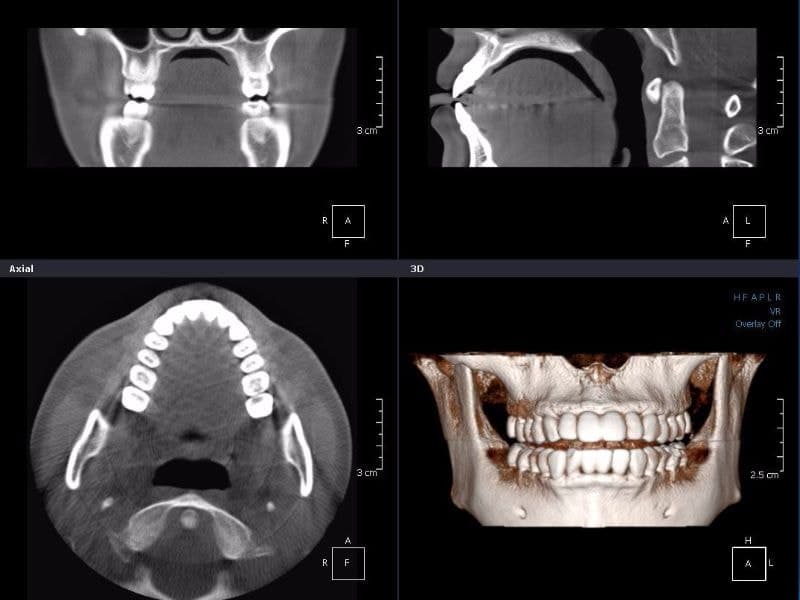

歯科用CTデジタルレントゲン

患者様に負担をかけず状況を詳しく知る

当院では、大学・総合病院クラスでしか撮影出来なかったCT撮影が可能です。

通常CT撮影は、多額の費用を払い、解析・診断等に1~2週間の時間を要します。

歯科用CT(3D)は、コンピュータを駆使したデータ処理と画像の再構成で、断層写真を得ることができる装置です。

根管治療、親知らずの抜歯や歯周病治療、歯列矯正など様々な分野で、CTによる正確な情報を元に、的確な治療計画を立てることが出来ます。

歯科用CTは少ない被爆で安心安全

一般的な医療向けCTは、歯科医院で撮影するパノラマ写真の約10倍以上の放射線を照射するといわれます。

当院の歯科用CTデジタルレントゲンは、従来のフィルムを使用したレントゲン撮影に比べ、人体に受ける放射線の量を約1/4~1/10に抑える事が可能です。

照射時間がかなり短く約10秒ほどで済み、安心安全です。